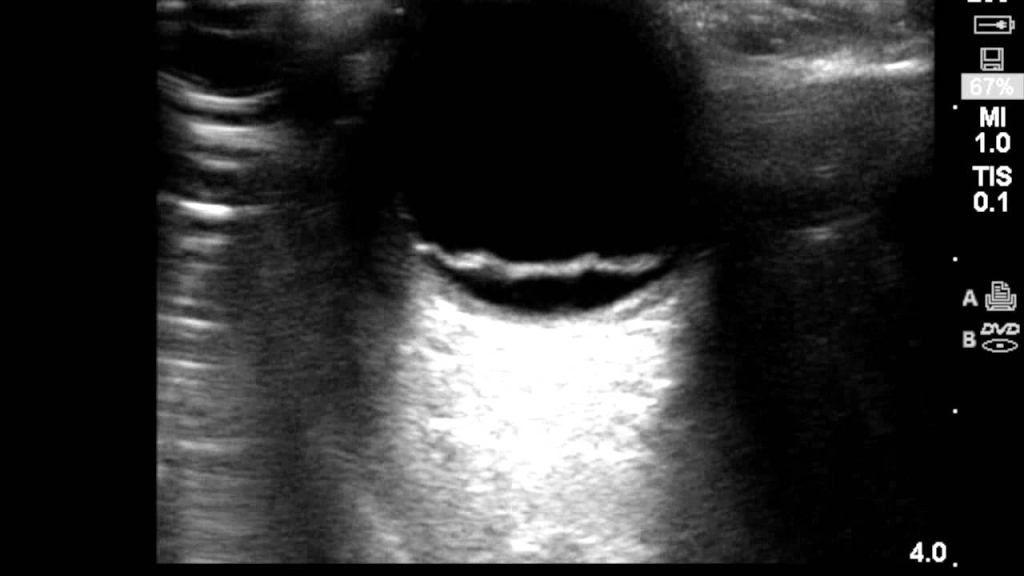

Ocular ultrasound was ordered and found a retinal detachment with concern for macular off detachment. The patient was then referred to an ophthalmologist for definitive care.

The following represents a retinal detachment which looks like the retina is floating in the vitreous instead of connected to the flat surface in the normal eye.

Retinal detachments will anchor at the posterior eye near the optic nerve, unlike most posterior vitreous detachments. The macula lies lateral to the optic nerve. When the retinal detachment goes all the way to the lateral portion of the optic nerve, suspect macular-off retinal detachment. When the retinal detachment does not reach the lateral portion of the optic nerve, suspect macular-on retinal detachment, which requires more emergent surgery to save eyesight.

In our case we found a macular-off retinal detachment, as seen in the pictures above.